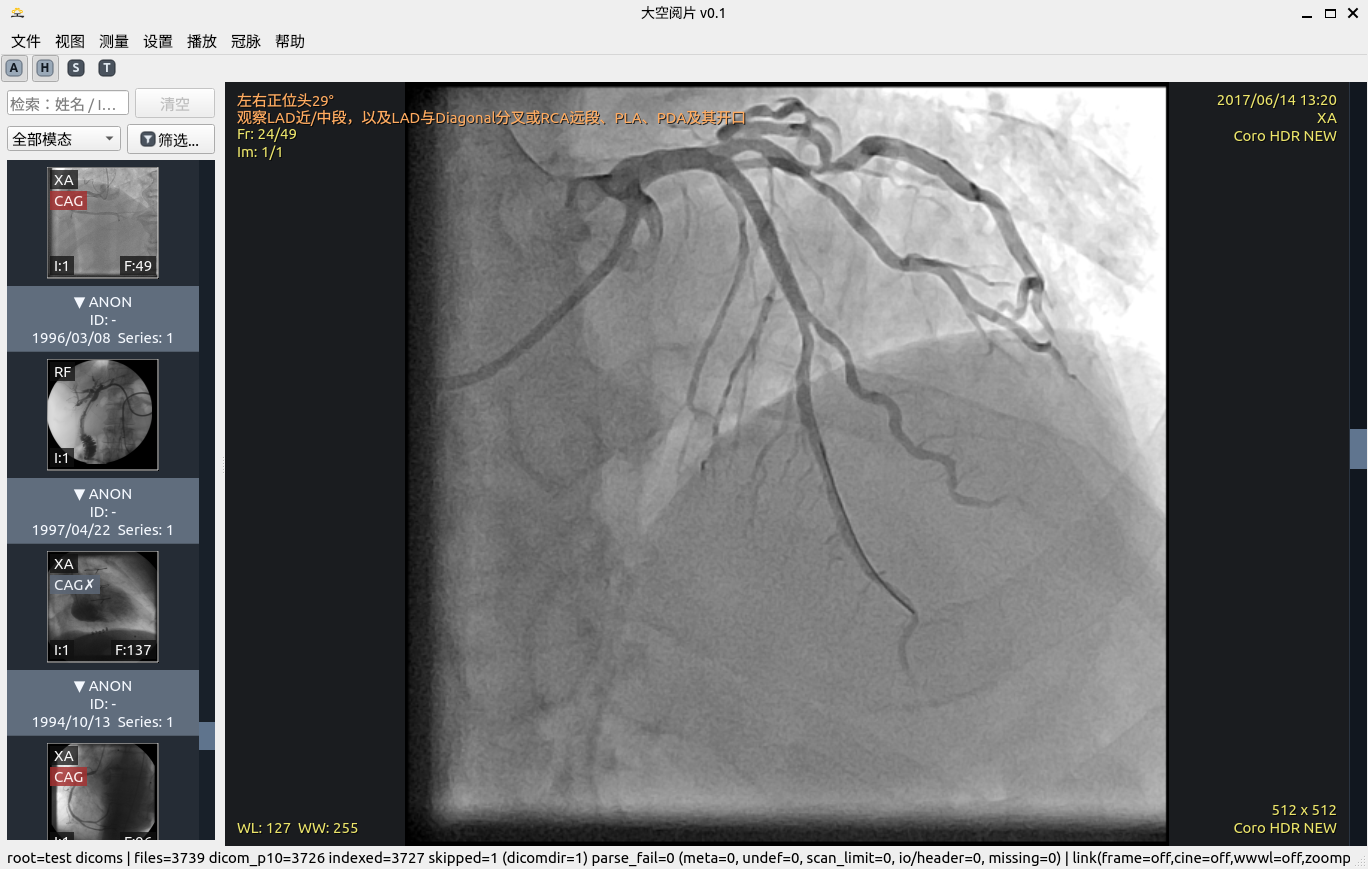

冠脉介入影像筛选

目标血管筛选

2. 冠脉介入影像筛选及目标血管筛选

先把“可做分析的序列”筛对,再进入定量流程,减少无效操作。

• 序列级规则筛选:结合 Modality、ImageType、描述信息与实例结构。

• 人工判定与算法判定双轨:可标记冠脉/非冠脉并随时回退。

• QCA 入口与序列资格联动,避免误入分析流程。